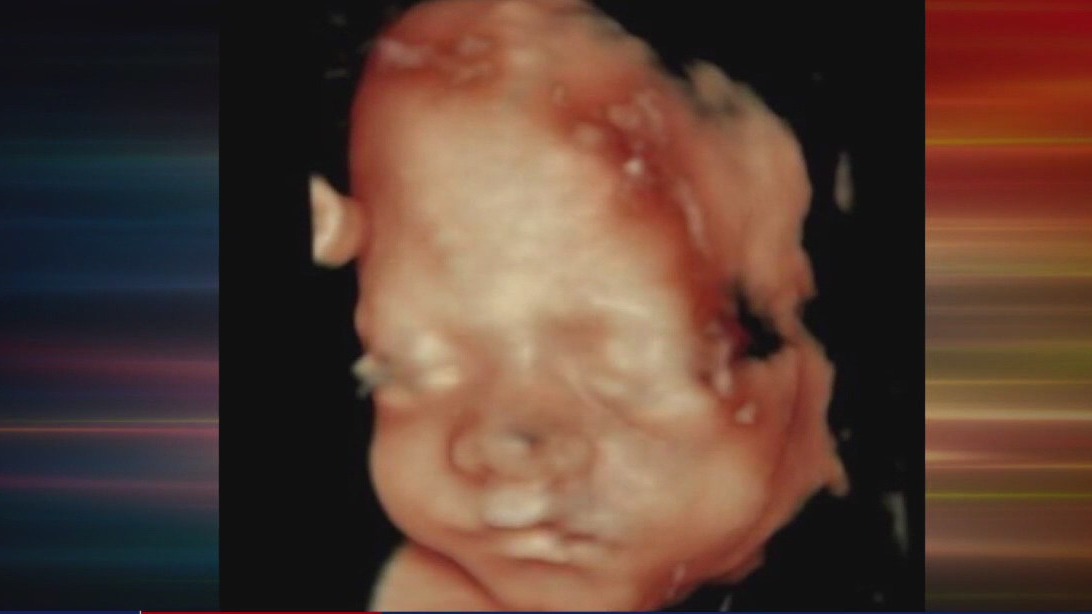

During the procedure, the amniotic fluid is replaced temporarily with carbon dioxide gas. On the O.R. monitor, we were able to observe what spina bifida looks like before the repair. In spina bifida, the neural tube, which should form the brain and spinal cord, doesn't close completely, leaving Violet's spinal cord and nerves exposed. Without intervention, her chances of walking would be minimal.